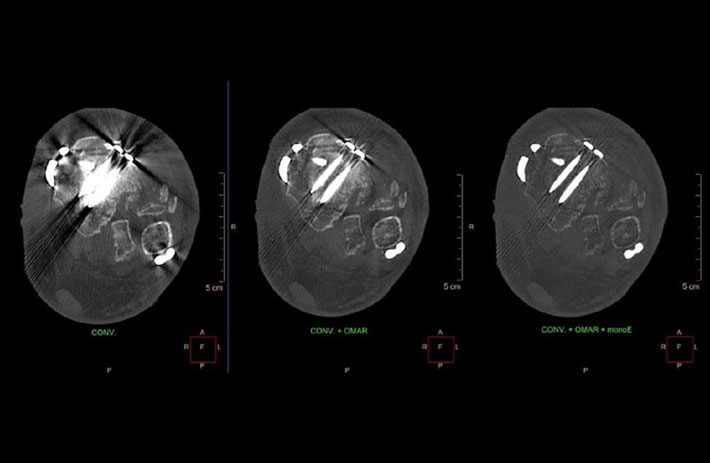

Mit dem Spektral-Detektor-CT werden Spektraldaten automatisch bei jedem Scan erfasst. Die Informationen stehen jederzeit auf der Scankonsole, der CT-Workstation sowie an jedem PACS-Arbeitsplatz zur Verfügung, sodass es nicht notwendig ist, den Patienten erneut zu scannen, bspw. wenn initial zufällige Anomalien festgestellt wurden. Dadurch profitieren Anwender durch eine höhere Diagnosesicherheit und weniger Nachuntersuchungen auf anderen bildgebenden Systemen. Unsere Fallsammlung zeigt, welchen klinischen Mehrwert der Spektral-Detektor-CT in unterschiedlichsten Anwendungsbereichen in der klinischen Routine bringt. Jede Woche gehen neue Fälle live.